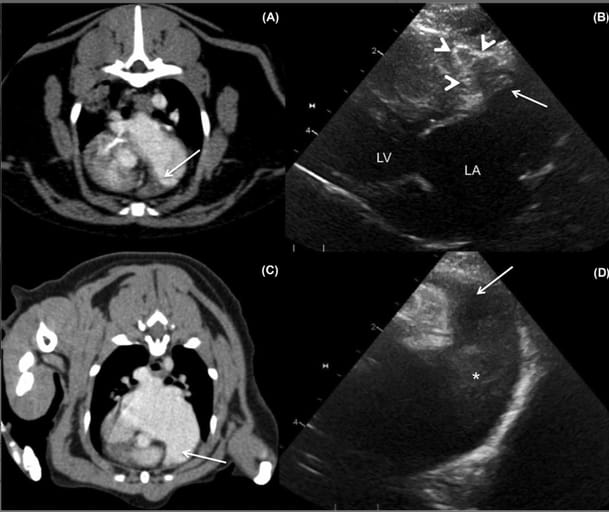

A, Transverse computed tomographic angiography of a patient with a dilated left atrium and left auricle and a large filling defect (presumed thrombus) (white arrow) occupying most of the left auricle. B, Oblique left apical parasternal long-axis echocardiographic image of the left auricle with corresponding thrombus that is similar in appearance (conforming to and occupying most of the left auricle). The white arrowheads outline the external margins of the left auricle. LA, left atrium; LV, left ventricle. The second set of images (C,D) is of a patient with severe left atrial enlargement and only spontaneous echo contrast identified on echo. C, Transverse thoracic computed tomographic angiography and oblique left apical parasternal long-axis view of the left auricle (D) with severely dilated left atrium/left auricle with no filling defects (thrombi) noted within the left auricle (white arrow). The asterisk highlights the spontaneous echo contrast within the left atrium. The right of the patient is on the left in the CT images and displayed in soft tissue window (window length, 40; window width, 400)